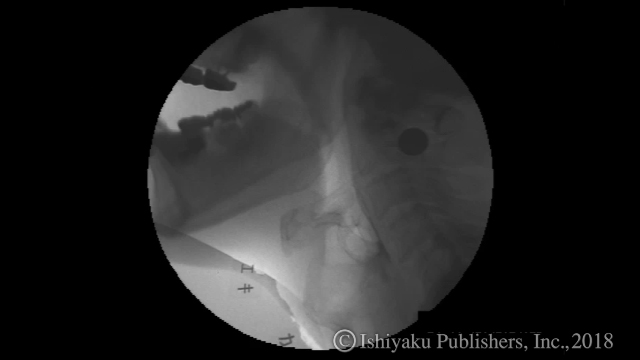

動画2 VF:脳卒中症例